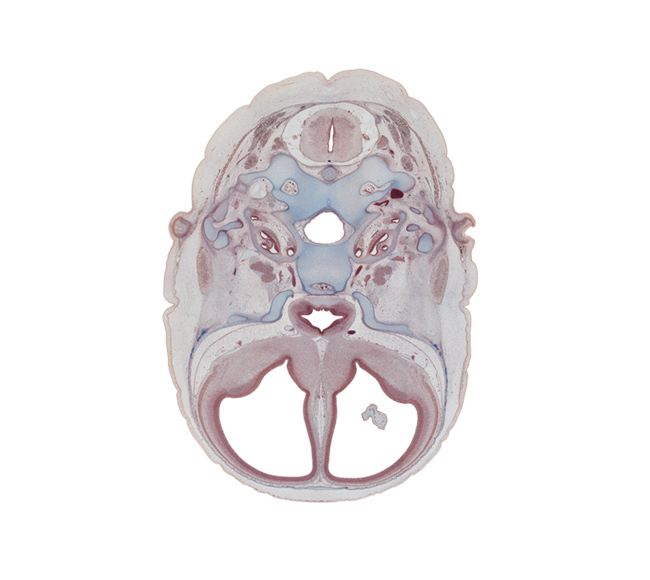

Carnegie Embryo #9226 | Location: 60-01-01

Keywords: C-1 spinal ganglion, anterior spinal artery, basi-occipital (basal plate), central canal, cochlear duct, cranial cavity, edge of choroid plexus, hypoglossal canal, hypophysial fossa, incus, intermediate zone, internal carotid artery, internal jugular vein, lamina terminalis, lesser wing of sphenoid, malleus, mandibular nerve (CN V₃), marginal zone, nucleus accumbens, ophthalmic nerve (CN V₁), optic chiasma (chiasmatic plate), optic groove, piriform cortex (paleopallium), styloid process, temporalis muscle, tuberculum sellae, ventricular zone

Source: The Virtual Human Embryo.